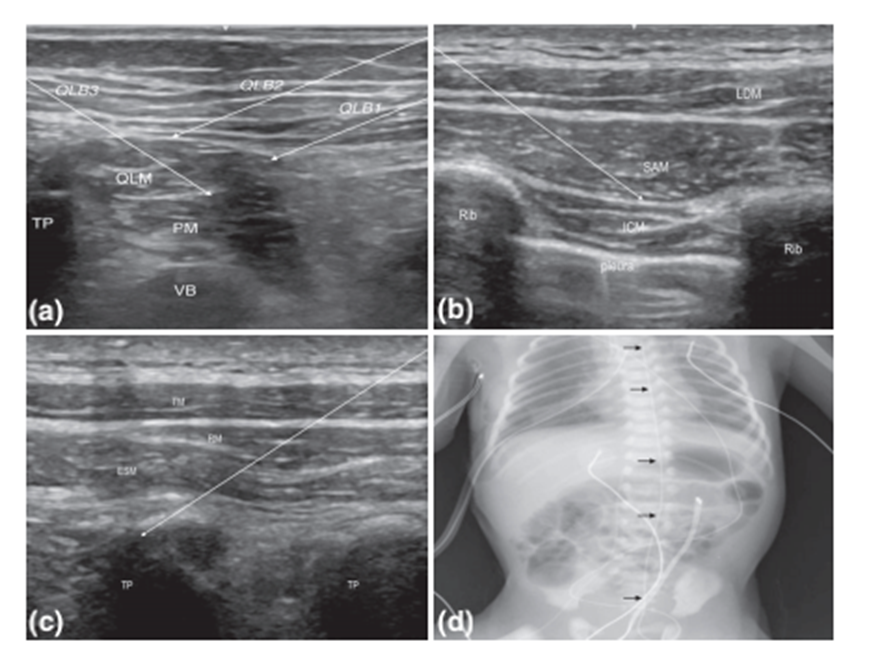

腰方肌阻滞在 2007 年的摘要中首次被描述,它是腹横肌平面阻滞的演变和扩展,意识到更多的腹横肌平面阻滞后入路导致更大的椎旁浸润,包括外侧 (腰方肌阻滞1)、后路 (腰方肌阻滞2) 和经肌肉(腰方肌阻滞3)技术(图 2a)。局麻目标是腰方肌与腹斜肌外侧腱膜、背阔肌或腰大肌(分别为腰方肌阻滞1、腰方肌阻滞2和腰方肌阻滞3)的筋膜间平面。腰方肌阻滞为成人的各种外科手术提供了成功的镇痛,包括剖腹产、剖腹探查术和全髋关节置换术。相对较快,这种有前途的技术被应用于儿科人群的下腹部手术,包括腹股沟疝修补术和造口闭合术。Hernandez等人描述了他们在10名接受各种腹部手术的儿童中使用一系列15个腰方肌阻滞的经验。15例患者中有6例(40%)的T7皮肤,15例患者中有10例(67%)的T8皮肤和15例患者中有14例(93%)的T9皮肤实现了感觉阻滞的最高程度。在所有患者中,镇痛的尾部延伸为T12-L1。

图2 (a)一例15个月大儿童腰方肌阻滞的超声解剖。箭头表示1型、2型和3型腰方肌的针尖位置 (b)16岁儿童前锯肌平面阻滞的超声解剖。箭头表示深锯齿前平面阻滞的针尖位置 (c)竖脊肌阻滞的超声解剖。箭头表示竖脊肌的针尖位置 (d)从尾部空间穿过不透射线的胸段硬膜外螺纹。

在成人成功后,前锯肌平面阻滞最近也被引入儿科人群。Blanco等人在2013年首次在成人中描述,前锯肌平面阻滞涉及在腋中线上的锯齿状前肌和背阔肌(浅表)或锯齿状前肌和肋间肌(深)之间的筋膜间平面中沉积局部麻醉剂第五根肋骨(图2b)。该区在同侧半胸的T2至T6水平提供可靠的皮区麻醉。

新型竖脊肌阻滞近年来引起了广泛关注。竖脊肌阻滞旨在为胸腰椎皮区提供镇痛,已应用于儿童和成人的一组异质外科手术,包括开腹和微创腹部和胸部手术、心脏手术、乳房手术和髋关节置换术。与椎旁和硬膜外阻滞相比,识别解剖标志的容易性和感知安全性有助于推动竖脊肌阻滞的日益普及。通过在竖脊肌下方注射局部麻醉剂并在椎骨横突水平从组织筋膜平面对肌肉进行水分离来完成阻滞(图 2c)。竖脊肌阻滞的性能通常使用旁矢状面超声引导技术来描述。注射的目标椎骨水平因手术报告和所需的镇痛区域而异。尸体和对比研究表明多椎体水平扩散与椎旁间隙以及背侧和腹侧支的浸润。

放置硬膜外导管的直接与尾部方法

尽管大量证据表明,连续硬膜外输注对新生儿和婴儿来说是一种安全有效的技术,但一些研究表明,该人群仍面临更高的手术并发症风险。鉴于新生儿和婴儿的解剖学差异,存在直接腰椎或胸硬膜外导管置入过程中因针头外伤导致神经损伤风险增加的担忧。这些解剖学差异包括较窄的硬膜外腔和较不致密的黄韧带,这可能使确认正确的针头位置更具挑战性。婴儿的另一个区别是硬膜外腔的脂肪组织含量,它是凝胶状的,松散地挤满了脂肪小叶。这种硬膜外流动性允许从更容易接近的尾部空间插入的硬膜外导管顺利通过。硬膜外导管可以从尾部空间向头侧推进到所需的腰椎或胸椎水平,然后使用各种技术进行确认(图 2d)。尾部和直接硬膜外方法都有优点和缺点,关于哪种方法最适合为婴儿提供腰椎或胸椎镇痛仍然存在争议。